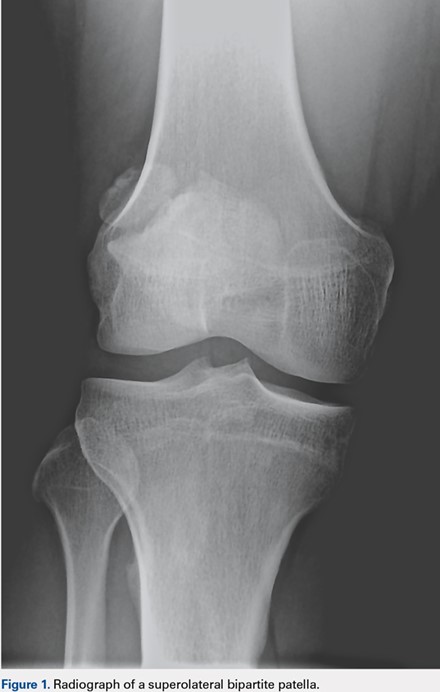

The most common extensor mechanism pathology present on preoperative imaging was proximal patella tendon thickening suggestive of patella tendinopathy. Thickening of the proximal portion of the patellar tendon was present in 15 of the 197 MRIs (prevalence, 7.6%) (Figure 3). The average width of this thickening was 8.49 mm (7.17-10.17 mm), and the average age of patients with radiographic evidence of patellar tendinopathy was 29.9 years (range, 20-43 years). Gender distribution was predominantly male (14 males, 1 female). Details of all extensor mechanism pathologies found are provided in the Table.